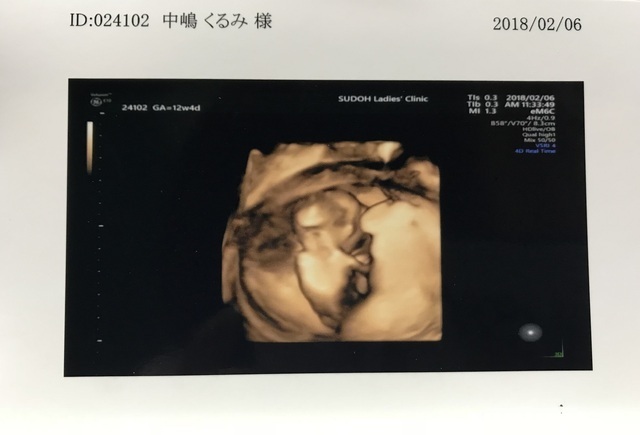

12週4日(12w4d・男の子)|krm113 さん(25歳)

エコー写真撮影時のエピソード:

このエコー写真を見たとき、家族みんなで笑ってしまいました。どんな顔なのか楽しみにしていたのですが、顔どころか、後ろを向いて体操座りをしているかの様な写真でした。まだ性別はわかっていなかったのですが、みんなからお腹の子は「スネオ(拗ねている様に見えたので)」と呼ばれるようになりました。この後、この子が生まれてくるまでエコー写真で顔をはっきり見せてくれることはなく、生まれてきたからやっと可愛い顔を見ることができました。